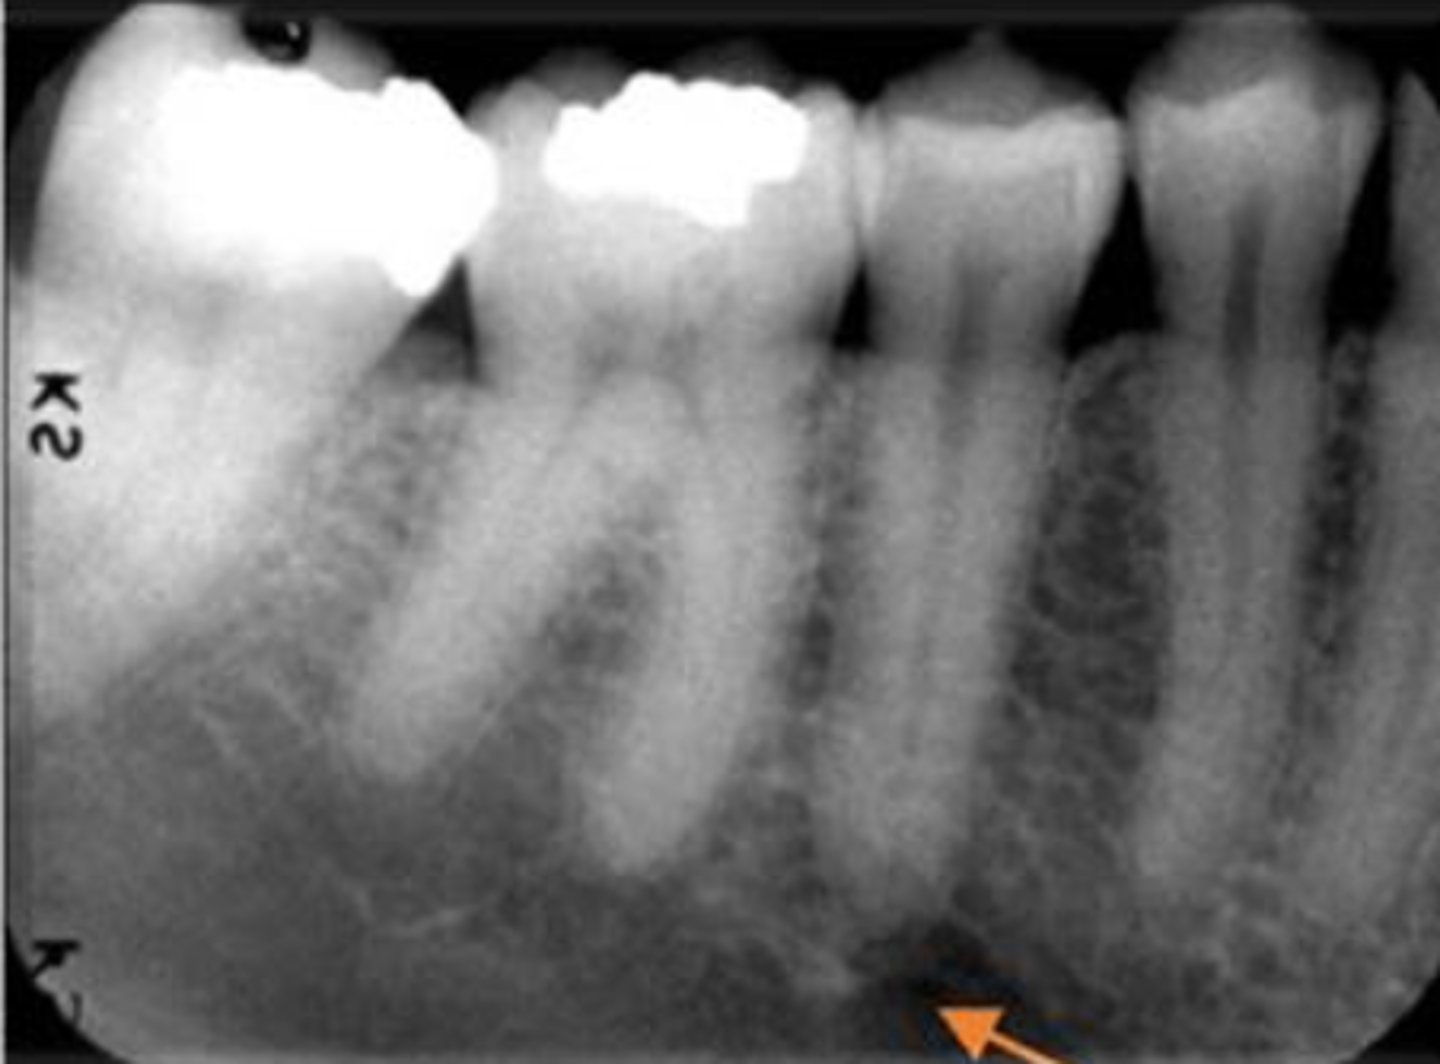

ID the structure with the purple arrow:

external oblique line

ID the structure with the green arrow:

inferior alveolar nerve canal